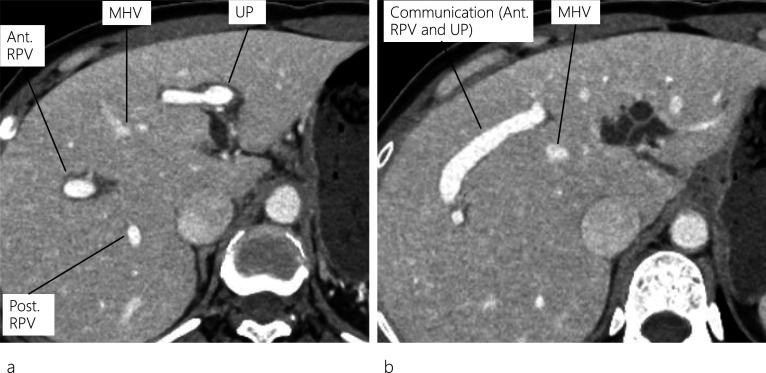

A 45-year-old female patient visited a local hospital with abdominal pain. Blood tests revealed elevated liver enzyme levels, and abdominal computed tomography (CT) revealed dilatation of both the common bile duct (CBD) and intrahepatic bile duct (IHBD). The patient underwent magnetic resonance cholangiopancreatography (MRCP) and endoscopic retrograde cholangiopancreatography (ERCP). MRCP showed CBD stones and stenosis at the confluence of B2 and B3 (Fig. 1a), while ERCP revealed IHBD stones in B2 and B4 (Fig. 1b), which were also observed on abdominal ultrasound (US) (Fig. 1c). Brushing cytology and biopsy at the site of the IHBD stenosis were negative for malignancy. Although the CBD stones were removed, the IHBD stones could not be; therefore, she was referred to our hospital for surgical treatment. Further examination could not be performed around the site of the IHBD stenosis because of impacted stones. Therefore, laparoscopic left hepatectomy was scheduled for suspected intrahepatic cholangiocarcinoma resulting from the impacted stones. However, to properly delineate the anatomy of the liver, enhanced CT was performed, which revealed a dilated IHBD in the left lobe and communication between the right PV and the umbilical portion (Fig. 2a, b). Based on the enhanced CT data, three-dimensional (3D) CT images were reconstructed, which revealed that instead of being located in the left Glisson’s sheath, both the left hepatic artery and bile duct were separated from the left PV (LPV) (Fig. 3a). They also revealed an LPV running through the ventral side of the middle hepatic vein (MHV) (Fig. 3b). Based on these findings, the patient was diagnosed with APB and scheduled to undergo laparoscopic left hepatectomy.

Regarding the anatomy of the bile ducts in patients with APB, Terasaki et al. [ref. 12] reported two patients with different bile duct characteristics, in whom the left hepatic duct ran either inside the liver along the PV or separately down into the common hepatic duct. The differences in running patterns between the PV and the bile duct can be explained from an embryological perspective. In our patient, an ordinary left bile duct was present, and IHBD stones were identified in the dilated B2 and B4. It is noteworthy that on routine preoperative plain CT images, the APB anomaly was not detected owing to the limitation of the images in outlining the detailed anatomy of the liver vasculature. However, the anomaly was detected on the preoperative enhanced CT images, which allowed us to reconstruct 3D images and view the detailed anatomy of the liver vasculature from different positions (neutral and left anterior oblique positions), as shown in Fig. 3.